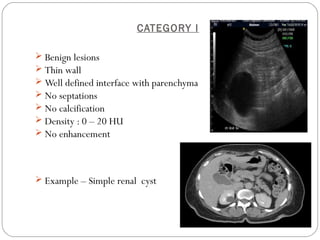

CATEGORY I

 Benign lesions

 Thin wall

 Well defined interface with parenchyma

 No septations

 No calcification

 Density : 0 – 20 HU

 No enhancement

 Example – Simple renal cyst